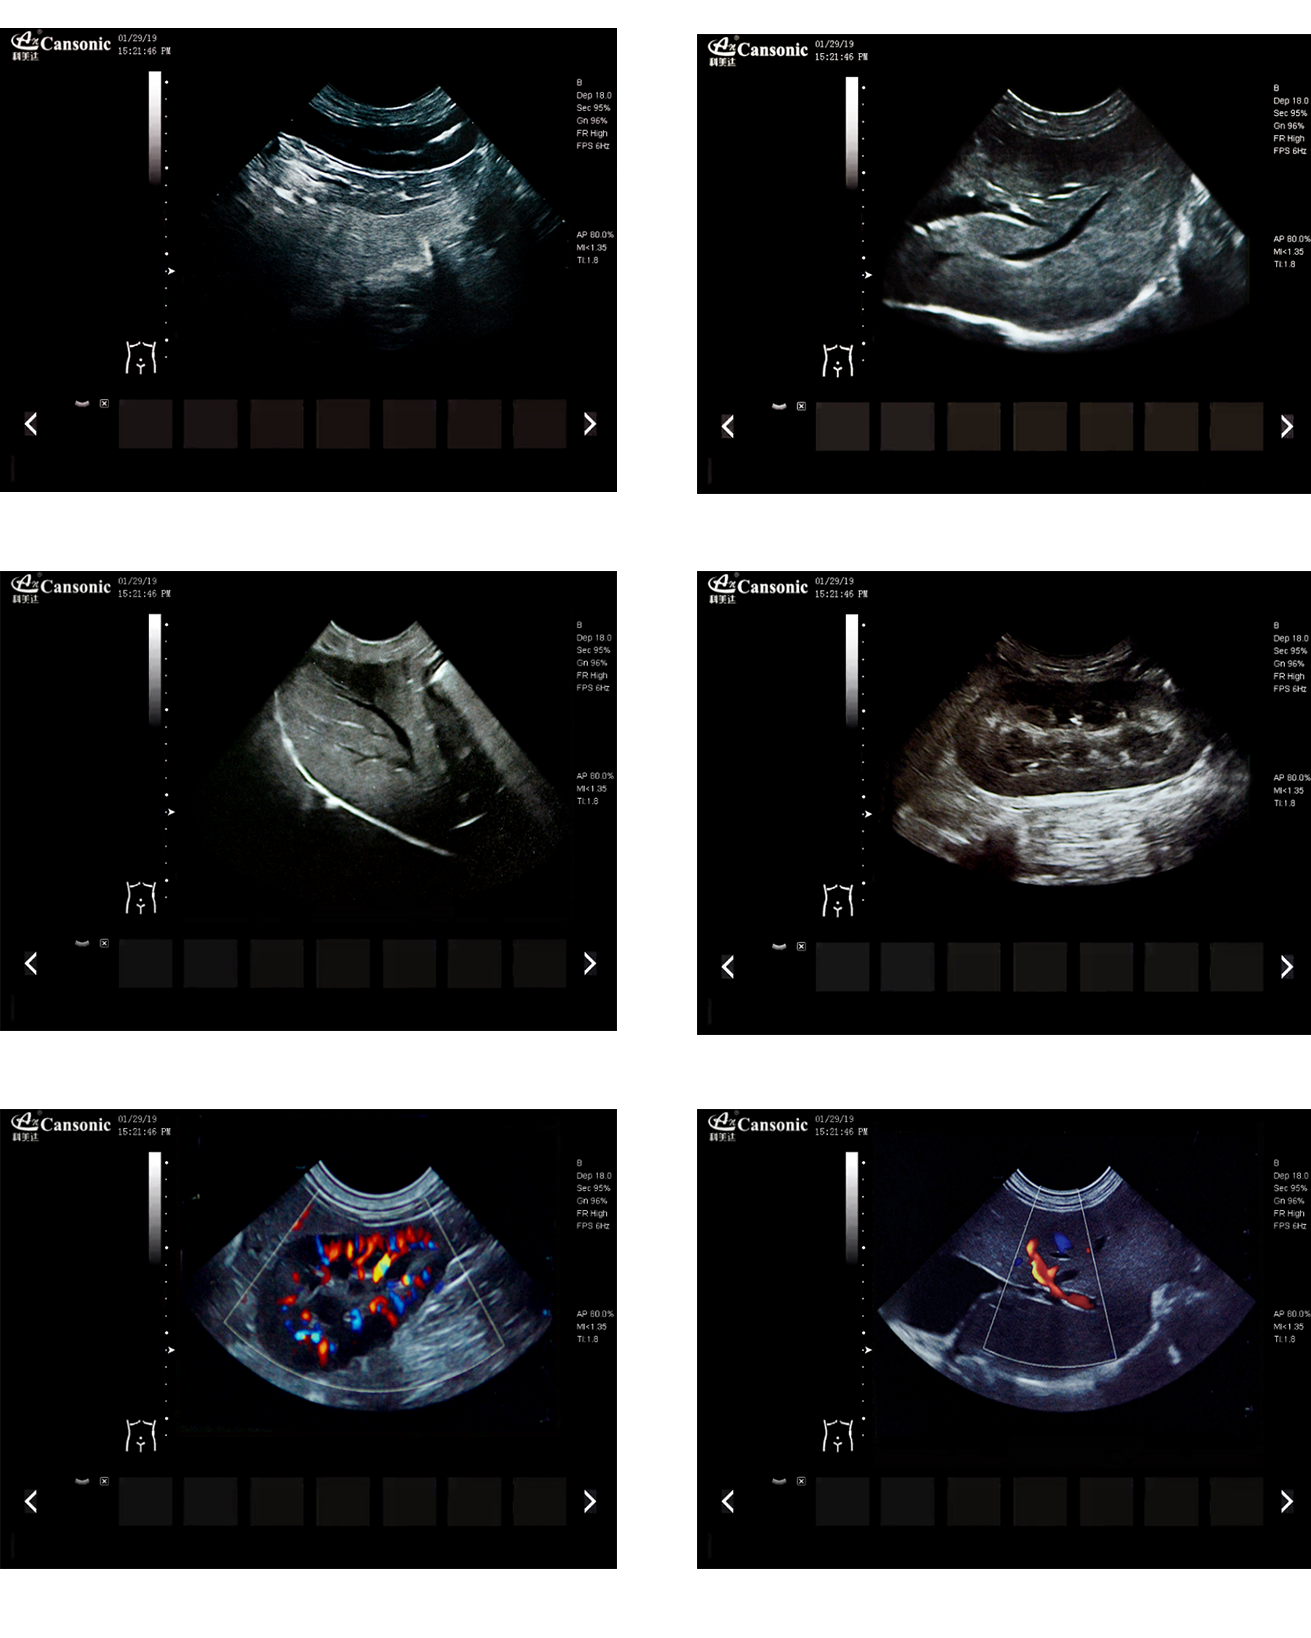

K2V

1、薈萃前沿成像技術(shù),實(shí)現(xiàn)高精與靈便的完美融合,提供完整的動物彩超診療方案

2、專業(yè)的獸用測量軟件,簡捷的工作流,適合犬、貓、馬、牛、羊等 各類大小動物

3、iClear斑點(diǎn)噪聲抑制抑制噪聲干擾,使動物組織結(jié)構(gòu)更清晰

4、具有廣泛的動態(tài)范圍,顯示出色的組織均勻性,減少了偽影及噪聲

5、精細(xì)血流識別技術(shù),增加了可疑病變更多的信息分析

6、先進(jìn)的算法帶來清晰的穿刺針顯示,降低穿刺活檢操作難度

7、圖像優(yōu)異,同時性能穩(wěn)定,每天能進(jìn)行大量的動物超聲檢查

臨床圖示